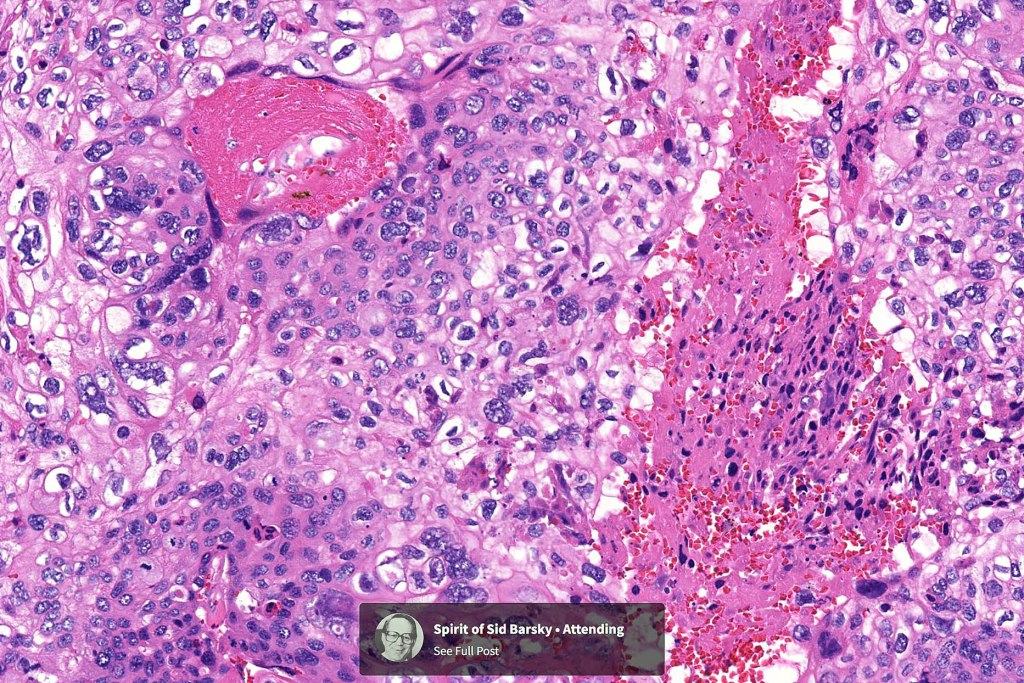

Histological features

•Nuclear pleomorphism and nuclear hyperchromatism

•Marked mitotic activity

•Abnormal mitoses

•Necrosis

•Stroma may be desmoplastic

•Spindle cell subtype